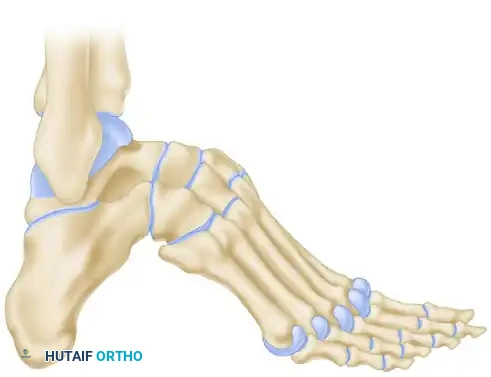

Siffert, Forster, and Nachamie Triple Arthrodesis

For severe cavus deformities, the Siffert, Forster, and Nachamie modification of the triple arthrodesis is highly effective. This technique focuses on resecting a specific dorsal wedge to plantarflex the forefoot and correct the arch.

Biomechanical Goal: A wedge of bone is removed by osteotomy from the midtarsal and subtalar joints. Crucially, the superior part of the talar head is retained to form a structural "beak."

The soft tissue structures anterior to the ankle joint are left undisturbed to maintain vascularity and anterior stability.

In the final position, the forefoot is displaced plantarward, and the dorsal cortex of the navicular is locked securely beneath the remaining "beak" of the talar head. This bony lock prevents dorsal subluxation of the midfoot and maintains the corrected arch height.